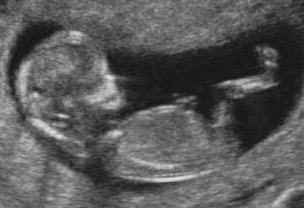

Attachment 31550

The first pic looks girly to me but then the second pic looks boyish. Sorry, I know that doesn't help!

Maybe boy based on second pic, but not the best pics, so could well be a girl too.